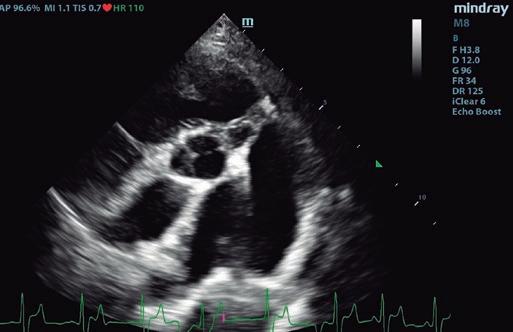

Boehringer Ingelheim España ha programado hasta final de año las Jornadas de Ecografía Avanzada patrocinadas por Vetmedin que recorrerán diversas ciudades del territorio nacional junto al referente Germán Santamarina. La finalidad de la iniciativa es brindar formación especializada y participativa a los especialistas en ecografía ambulante, un colectivo con necesidades muy específicas al cual Boehringer Ingelheim brinda su apoyo.

Las jornadas comenzaron en Barcelona y Alicante los días 21 y 22 de junio, respectivamente. Madrid, País Vasco y Andalucía y Canarias serán las siguientes durante las semanas del 23 de octubre y del 13 de noviembre. Todas las sesiones tienen una duración de medio día y se desarrollan en formato de mesa redonda a partir de las 15:00 h.

Con el objetivo de promover una experiencia más cercana e interactiva, las sesiones se organizan en grupos pequeños, con un límite de 10 a 15 participantes por sesión.